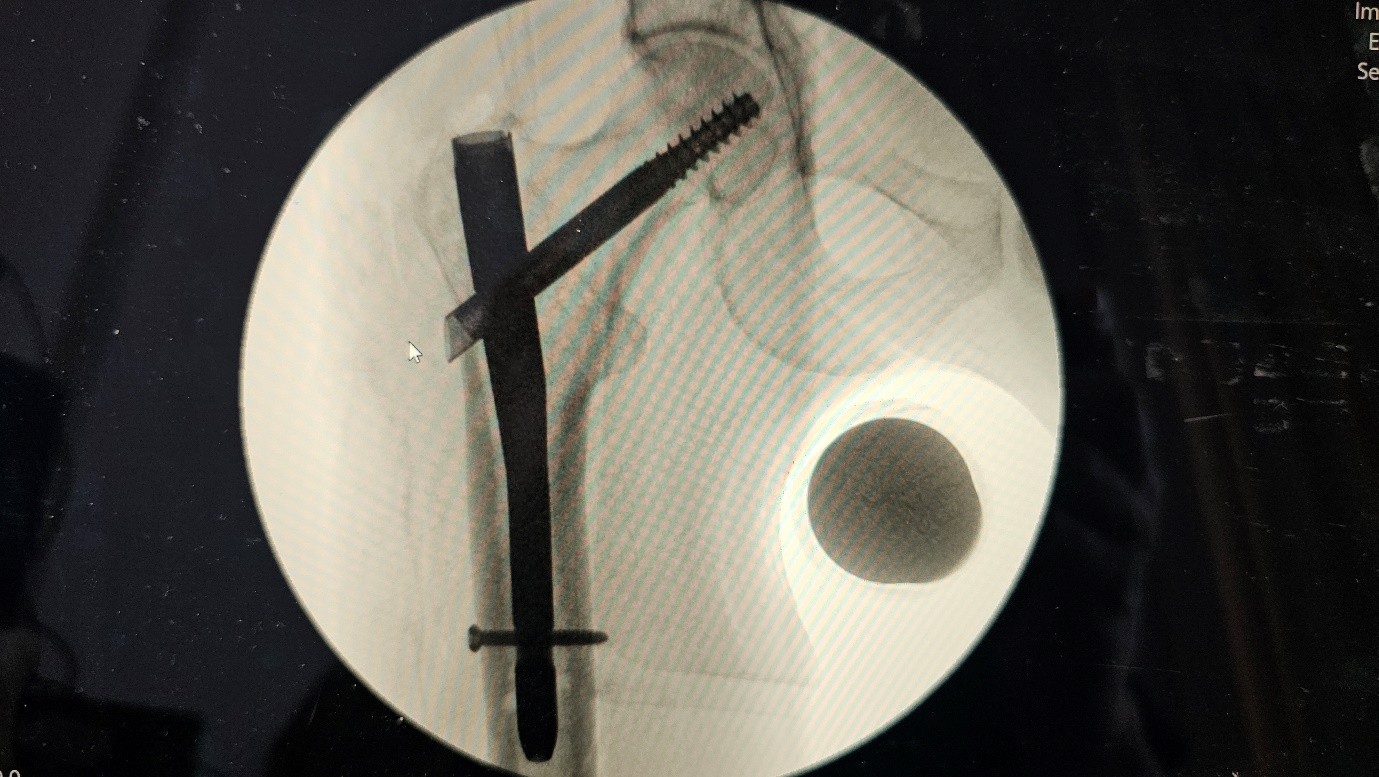

Post first surgery :

Fig 3

Fig 4

Fig 5

Figure 3

Figure 4

Figure 5